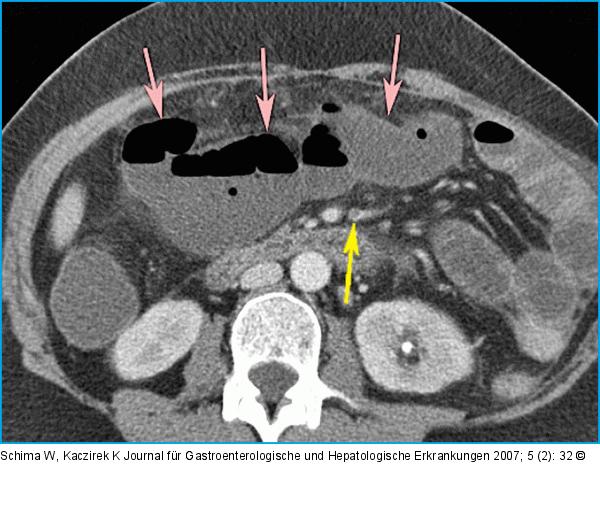

Abbildung 1A: CT-Bild in axialer Schichtführung Das CT-Bild in axialer Schichtführung zeigt angedeutet die Embolie in der A. mes. sup. (schwarzer Pfeil) sowie eine Dilatation der Ileumschlingen (weiße Pfeile). |

Das CT-Bild in axialer Schichtführung zeigt angedeutet die Embolie in der A. mes. sup. (schwarzer Pfeil) sowie eine Dilatation der Ileumschlingen (weiße Pfeile). |